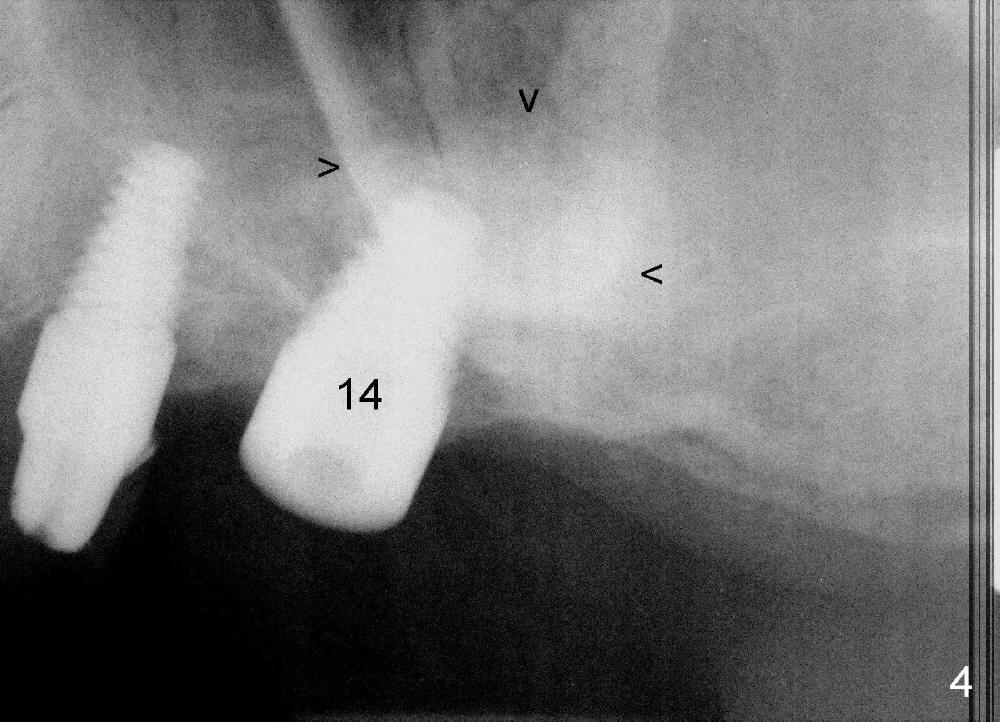

A lateral sinus window is created with a round diamond bur in high speed handpiece with copious irrigation as planned (Fig.3 W). The sinus membrane is lifted without tear. With the membrane protected with 2x2 gauze, an osteotomy (Fig.3 <) is developed at the site of the tooth #14 with 2 mm pilot drill, 2.5-3.5 mm reamers, 5x11 mm tap (Fig.1: T) and 6x11 mm tap. A synthetic bone graft (Osteogen 300-400 micron) is placed in the sinus before placement of 6x11 mm implant (Fig.4: 14). More of the synthetic bone mixed with autogenous bone is added superficial to the apex of the implant inside the sinus. The flaps are sutured.

The position and trajectory of the osteotomy (Fig.1 T) and subsequently those of the implant (Fig.4: 14) are aided by a surgical stent, which is fabricated from the model (Fig.2).